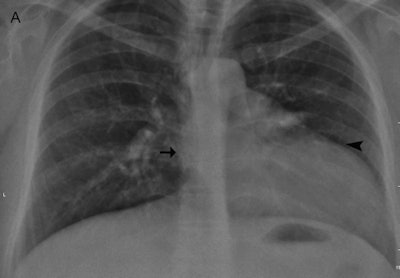

In one case the authors encountered at their hospital, an otherwise healthy 35-year-old woman was referred for ovarian cyst surgery. A chest radiograph demonstrated marked displacement of the cardiac silhouette to the left with flattening and elongation of the left ventricular contour (Snoopy sign) and obliteration of the right cardiac border (see figure).

"Chest radiographs may reveal levoposition of the heart, elevation of the cardiac apex, and elongation and flattening of the left border with prominence of the main pulmonary artery, which is separated from the aortic knob by interposed lung tissue," explained Dr. Stavroula Theodorou and Dr. Daphne Theodorou, PhD, radiologists at General Hospital "G. Hatzikosta" in Ioannina.